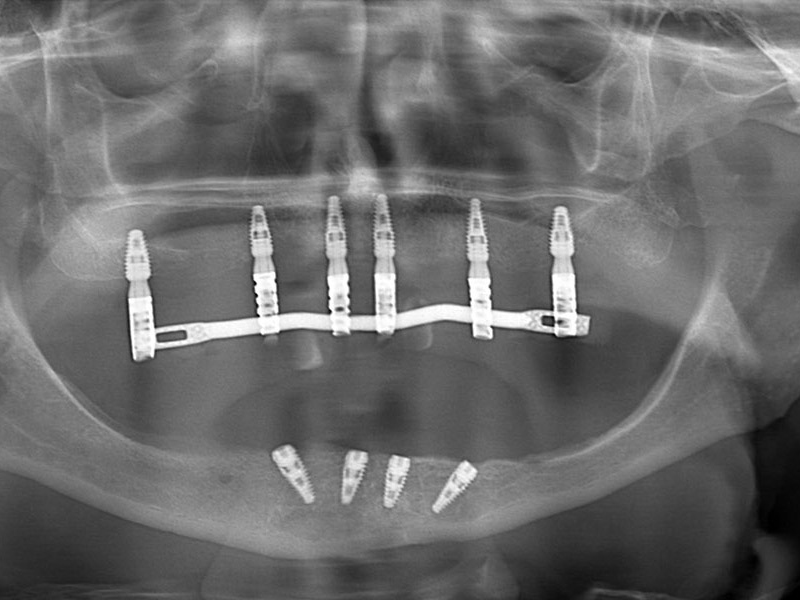

The All on 8 dental implant system consists of positioning 8 dental implants per dental arch, functioning as "anchors" for a fixed and non-removable dental bridge. This system is recommended in cases where the patient has lost more than 80% of his natural teeth.

These dental implants will support a fixed dental bridge (permanently cemented on the implants) between 12 and 14 units (teeth). Before receiving All-on-8, the patient must have enough bone to support the implants. If there is not enough bone, a bone graft is needed. An All-on-8 requires more bone and more bone strength than an All-on-4.

Extreme precision of implant placement

Send us the dental x-ray and leave us your contacts, you will get a free quote in the shortest time possible. Here you can load the x-ray